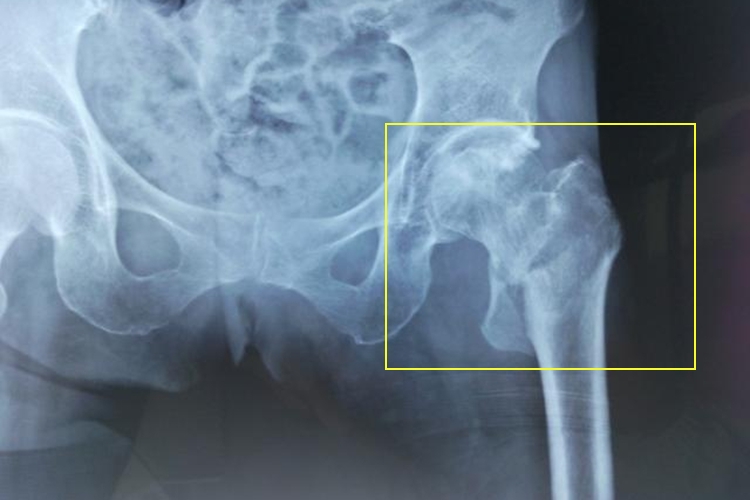

股骨粗隆间骨折后,患者局部会出现疼痛、肿胀、淤斑,下肢外旋畸形明显,可达90°,不能活动。X线拍片可见股骨粗隆间骨折,骨折线由大粗隆斜行向内下而达小粗隆,小粗隆可碎裂成蝶形骨片,折端呈髋内翻畸形。或骨折线由小粗隆上斜行向外下而达大粗隆基底部,近折端外展外旋,远折端向内上移位。